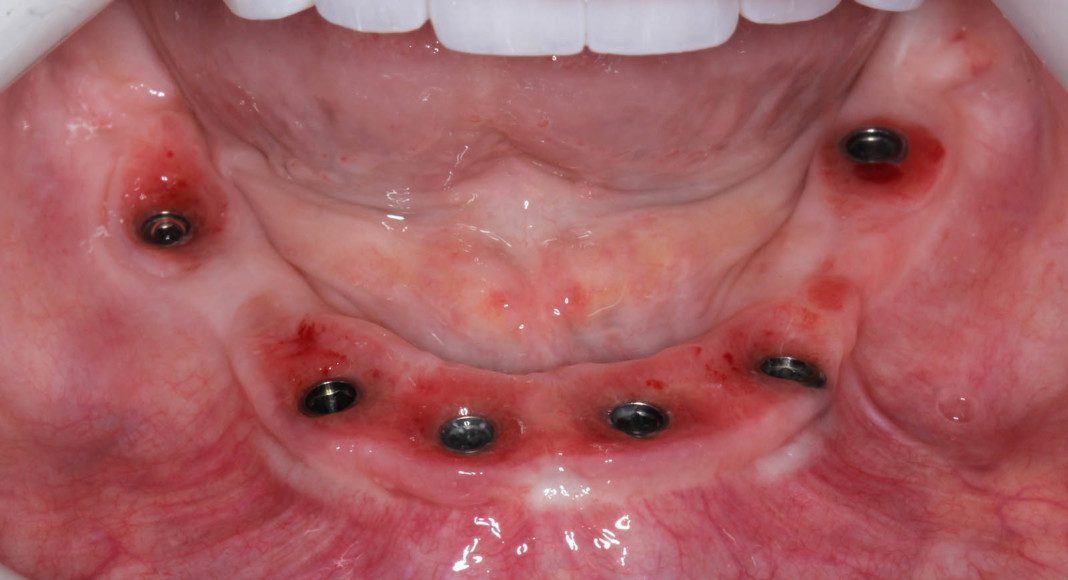

Occlusal (mirror) view of the upper implants and soft tissue. The redness are areas where the temporary bridge is shaping the tissues for future perfection.